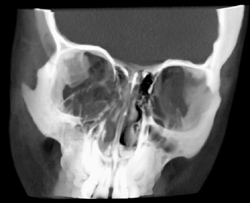

Orbital Trauma